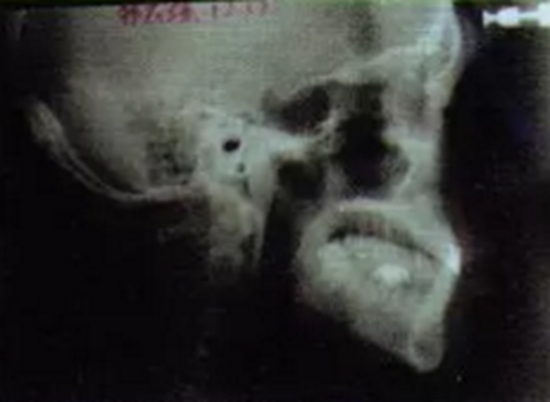

曲面全景片可見1為樁核冠、根尖1/3欠充,但未見陰影。1根方見多生牙高密度影。6遠(yuǎn)中根外吸收、根管欠充,根尖周圍可見透射陰影,牙周膜增寬。上前牙及63近遠(yuǎn)中牙槽骨度輕度水平吸收。1牙根尖片見其牙周膜清晰度尚可,未見根骨粘連。頭顱側(cè)位片測量結(jié)果示患者為I類、均角骨面型,上前牙和下前牙唇傾度減?。▓D3)。

圖4術(shù)前頭顱側(cè)位片